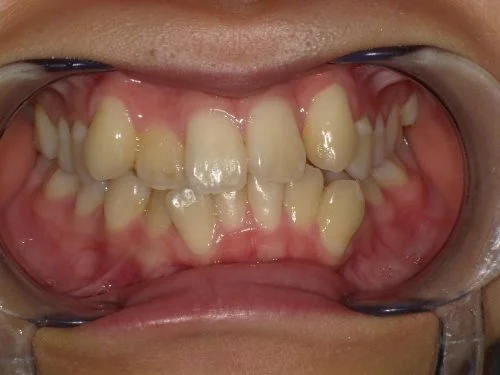

<症例3>前歯のクロスバイトでお悩み

右上の前歯2本が反対に咬合している、いわゆるクロスバイトが主訴でご来院なさいました。

主訴以外の部分には大きな叢生はなく、また患者様も装着時間をしっかり守ってくださったので約6ヶ月で改善することができました。

患者様と症状

主訴:上の前歯が出ている

性別・年齢:20代女性

問題点:上顎左側側切歯のクロスバイト、叢生

診断:前歯部の叢生を伴うアングルⅠ級の不正咬合

主なリスク:矯正中一時的に咬合しにくくなる、歯肉退縮

症状:叢生(そうせい) 上顎前突(じょうがくぜんとつ)

治療内容

治療期間:6ヶ月

治療費用:495,000円(税込)

プラン:14枚コース/ライトプラン

抜歯:親知らずのみ抜歯

再診治療費:無し

追加治療費:無し

保定装置費:無し

治療前後の写真

・2本の前歯が前突しておりましたが、矯正で自然な歯並びになりました。

・前歯の1本が下の歯の裏側に噛み合うクロスバイトになっていましたが、矯正で改善されました。